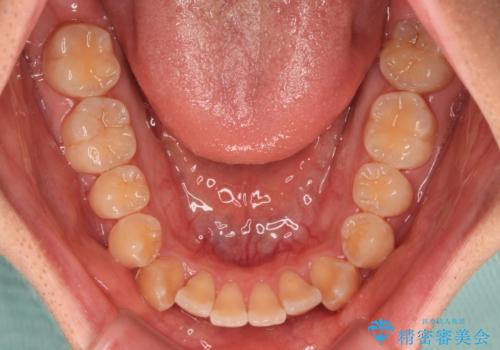

オープンバイトは舌の突出癖により誘発され、治療後も突出癖が残っている容易に後戻りしてしまいます。

治療期間を短縮するためにも、舌突出癖の改善が極めて重要となります。

特にインビザラインではIPRという歯と歯の間を削る処置を多用するため、後戻りによりスペースが生じやすくなるため、治療初期段階での舌のトレーニングが必須となります。